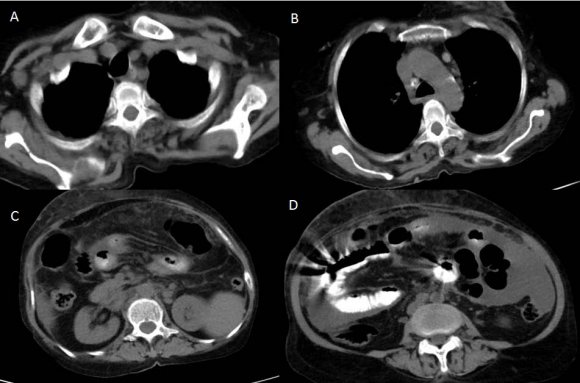

Computed axial tomography (CT scan) of the thorax (Figures: 1-3) showed small patchy areas of alveolar consolidation in the peripheral portion of the right middle lobe and lingula, and the left perihilar region. Multiple small nodular lesions were noted in the peribronchial region in the anterior basal segment of the right lower lobe and segmental bronchi of lingula. Multiple lymph nodes of size 5 to 10 mm were noted in pretracheal, right paratracheal, subcarinal region, in prevascular space and aortopulmonary window. Bilateral axillary lymph nodes also noted, the largest right axillary lymph node measured 13x13mm. Most of the lymph nodes showed peripheral enhancement with central hypodense areas of necrosis. Lymph nodes were also noted in the right juxtadiaphragmatic region, the largest measuring 13x9mm. There was no pleural effusion on either side.

CT scan of the abdomen and pelvis (Figures: 4-8) showed changes of fatty infiltration in the liver. Multiple well-defined lymph nodes of size 1 to 2 cms were noted at portahepatis, peripancreatic region, celiac axis, left renal hilum, preaortic and para-aortic regions, precaval and paracaval regions and in right internal iliac region. Most of the lymph nodes showed peripheral enhancement with central hypodense areas of necrosis. A conglomerated matted lymph nodal mass of size 35 x 24 mm noted in the precaval region. Multiple ill-defined and nodular soft tissues infiltrate noted within the mesentery. Moderate ascites noted with mild peritoneal enhancement without septations. Ileo-caecal junction and other bowel loops appeared normal. IVC distal to renal veins showed persistent filling defect of size 10 (Anteroposterior) x 16 (Transverse) mm extending over a length of 67mm with peripheral enhancement in contrast study extending to right common iliac vein suggestive of IVC and right common iliac vein thrombosis.